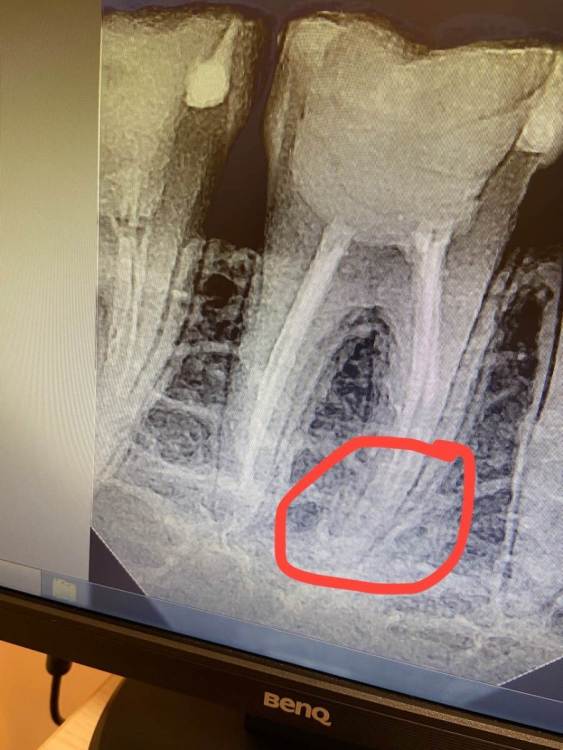

Непролеченный канал

День добрый.  Зуб 46. Ставили 3 раза пломбы. Зуб  беспокоил. Перелечивали каналы 2 раза.  ( лечу зуб с октября 2022 по май 2023 в одной клинике). Сейчас сделал снимок в другой клинике и врач сказал, что канал не пройден.  Посоветуйте что мне делать.  Тк в своей клинике, говорят о непроходимости канала.  Но перед лечением меня об этом не предупреждали.  И утверждают что работа выполнена качественно и зуб болеть не может.4257B457-3CAC-4860-8834-D9665E03AC73.thumb.jpeg.7d5ae8f365145e14961964a29ce16eb2.jpeg

нужно найти врача, который специализируется  на перелечивании корневых каналов, прийти к нему, он посмотрит, сделает компьютерную томографию и от этого уже решать в какую сторону двигаться